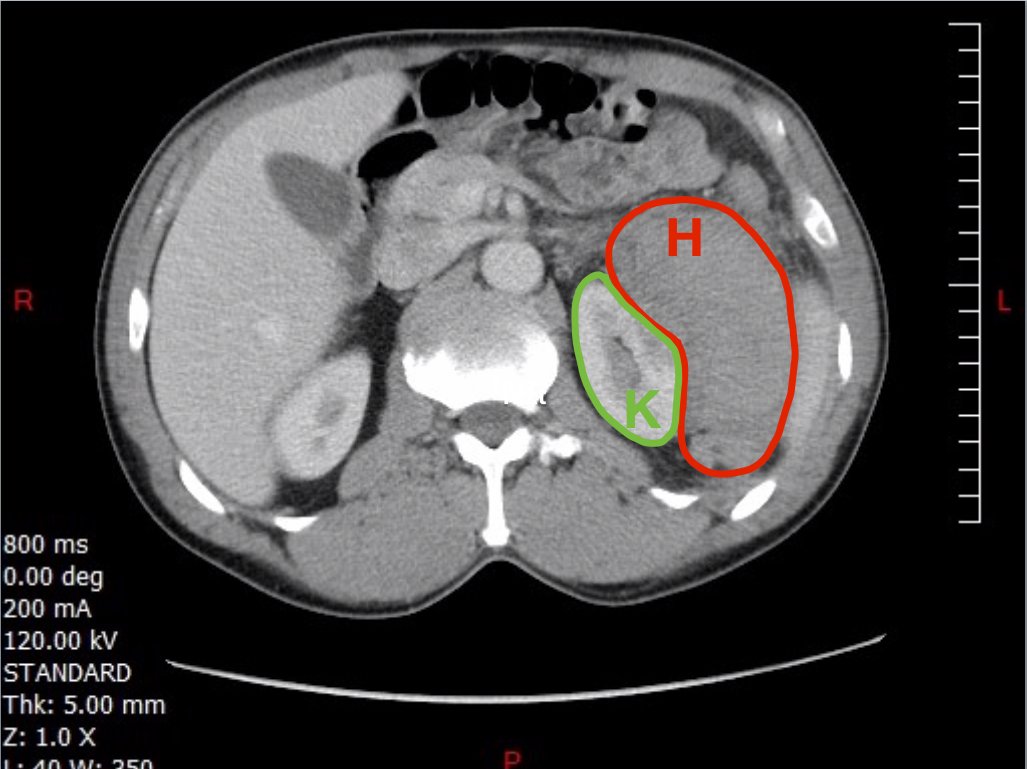

A 49-year-old male presents for evaluation of hematuria and left flank pain after mechanical fall down stairs four days ago. Point-of-care ultrasound (POCUS) focused assessment with sonography in trauma (FAST) exam demonstrated subcapsular renal hematoma. Once a subcapsular hematoma is recognized the provider should keep in mind that this condition may be managed conservatively in patients with two normally functioning kidneys, but may require urgent intervention if the patient is at risk for significant renal disease, such as a single kidney. The use of bedside ultrasound can expedite diagnosis and care for these patients, and allow proper consultants to be contacted early. Some consultants that may need to be consulted include nephrology, urology, and/or internal medicine. This case report emphasizes the utility of the FAST exam for patients presenting for non-acute trauma. The FAST exam can be utilized not only to identify free fluid in the abdomen and pelvis but also to visualize organs and the surrounding tissues for abnormalities after a trauma.